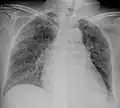

![]() | |

Chest X ray showing miliary tuberculosis | |

Miliary tuberculosis is a form of tuberculosis that is characterized by a wide dissemination into the human body and by the tiny size of the lesions (1–5 mm). Its name comes from a distinctive pattern seen on a chest radiograph of many tiny spots distributed throughout the lung fields with the appearance similar to millet seeds—thus the term "miliary" tuberculosis. Miliary TB may infect any number of organs, including the lungs, liver, and spleen.[2] Miliary tuberculosis is present in about 2% of all reported cases of tuberculosis and accounts for up to 20% of all extra-pulmonary tuberculosis cases.[3]

A case of miliary tuberculosis in an 82-year-old woman:

- X-ray, 22 days after onset, showing extensive bilateral reticulo-nodular infiltrates